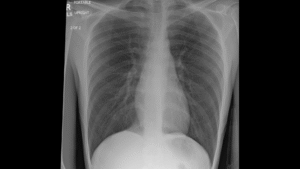

A Multi-Institutional Chest Radiograph Dataset To Evaluate AI Generalizability (MAIDA)

Led by researchers at Harvard, a large multi-institutional international effort is underway to build a dataset of chest radiographs to train and evaluate AI interpretation models. Ultimately, these models could have applications aiding in diagnostic processes in various clinical settings. The creation of a public repository of chest imaging data collected from a range of clinical settings and populations internationally will enable exploration of the extent and limit of generalizability of machine learning models with an eye toward equity and safety. The consortium of participating hospitals is expanding rapidly, and we are continually looking for site PIs interested in responsible applications of AI models in clinical settings to join.

Medical Imaging and Data Resource Center (MIDRC) Data contribution

The ImgARC Lab is helping to contribute data to a national repository of images and other clinical data related to COVID-19 in order to fuel studies advancing our understanding of how to diagnose, monitor, and treat the virus. Imaging and clinical data related to COVID-19 is gathered, deidentified, and uploaded to the repository for use in research.

Funding: RSNA MIDRC Award